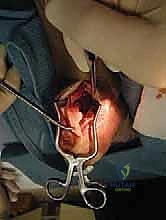

الخطوة الأولى: الفتح الجراحي والوصول للوتر

يقوم الدكتور هطيف بعمل شق جراحي دقيق في الجزء الخلفي من الكاحل، عادة في خط الوسط أو مائل قليلاً لتجنب الأعصاب. يتم كشف وتر أخيل المتضرر والجراب الزلالي الملتهب.

الخطوة الثانية: التنضير الجذري (Debridement)

هذه الخطوة تتطلب دقة متناهية. يتم شق وتر أخيل طولياً للوصول إلى الأنسجة التالفة. يقوم الجراح بإزالة جميع الأنسجة الميتة، والندبية، والتكلسات العظمية الموجودة داخل الوتر. في الحالات الشديدة، قد يتم فصل جزء كبير من الوتر عن عظم الكعب لتنظيفه بالكامل.

الخطوة الثالثة: استئصال تشوه هاغلوند (Calcaneoplasty)

بمجرد كشف عظم الكعب، يستخدم الدكتور هطيف أدوات جراحية دقيقة لإزالة النتوء العظمي الخلفي (تشوه هاغلوند) بالكامل. يتم تنعيم سطح العظم لضمان عدم احتكاكه بالوتر مستقبلاً. هذه الخطوة حاسمة لمنع عودة الألم.

الخطوة الرابعة: حصاد وتر (FHL)

يتم تحديد مسار وتر العضلة الطويلة المثنية لإبهام القدم. يقوم الجراح بتحرير الوتر من ارتباطاته السفلية في منتصف القدم، ويسحبه إلى منطقة الكعب. يتم التأكد من الحصول على طول كافٍ من الوتر لعملية النقل.

الخطوة الخامسة: تحضير النفق العظمي

يتم حفر نفق عظمي دقيق جداً داخل عظم الكعب (Calcaneus) باستخدام مثقاب جراحي خاص. يجب أن يكون النفق في الزاوية والموقع الميكانيكي الحيوي المثالي لضمان أقصى قوة شد.

الخطوة السادسة: تثبيت وتر (FHL) داخل عظم الكعب

يتم تمرير وتر (FHL) الذي تم حصاده عبر النفق العظمي. ولتثبيته بأقصى درجات المتانة، يستخدم الدكتور هطيف براغي تداخلية (Interference Screws) متطورة قابلة للامتصاص أو من التيتانيوم، بالإضافة إلى خطاطيف معدنية (Suture Anchors). هذا التثبيت المزدوج يضمن عدم تحرك الوتر تحت ضغط الوزن.

الخطوة السابعة: إعادة بناء وتر أخيل والإغلاق

بعد تثبيت الوتر الجديد، يتم إعادة خياطة ما تبقى من وتر أخيل الأصلي حول وتر (FHL) الجديد لدمجهما معاً ككتلة واحدة قوية. يتم إغلاق الجرح بطبقات تجميلية دقيقة لتقليل الندبات، ويوضع الكاحل في جبيرة بوضعية انثناء أخمصي بسيط (Plantar flexion) لتقليل الشد على الأوتار المصلحة.